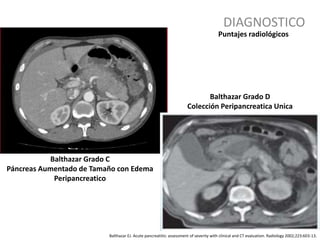

DIAGNOSTICO

Balthazar EJ. Acute pancreatitis: assessment of severity with clinical and CT evaluation. Radiology 2002;223:603-13.

Puntajes radiológicos

Balthazar Grado C

Páncreas Aumentado de Tamaño con Edema

Peripancreatico

Balthazar Grado D

Colección Peripancreatica Unica